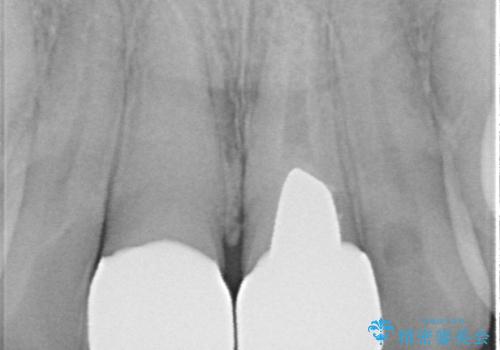

左右対称の2本の歯にセラミッククラウンを装着したことで、調和の取れた審美的な口元となりました。